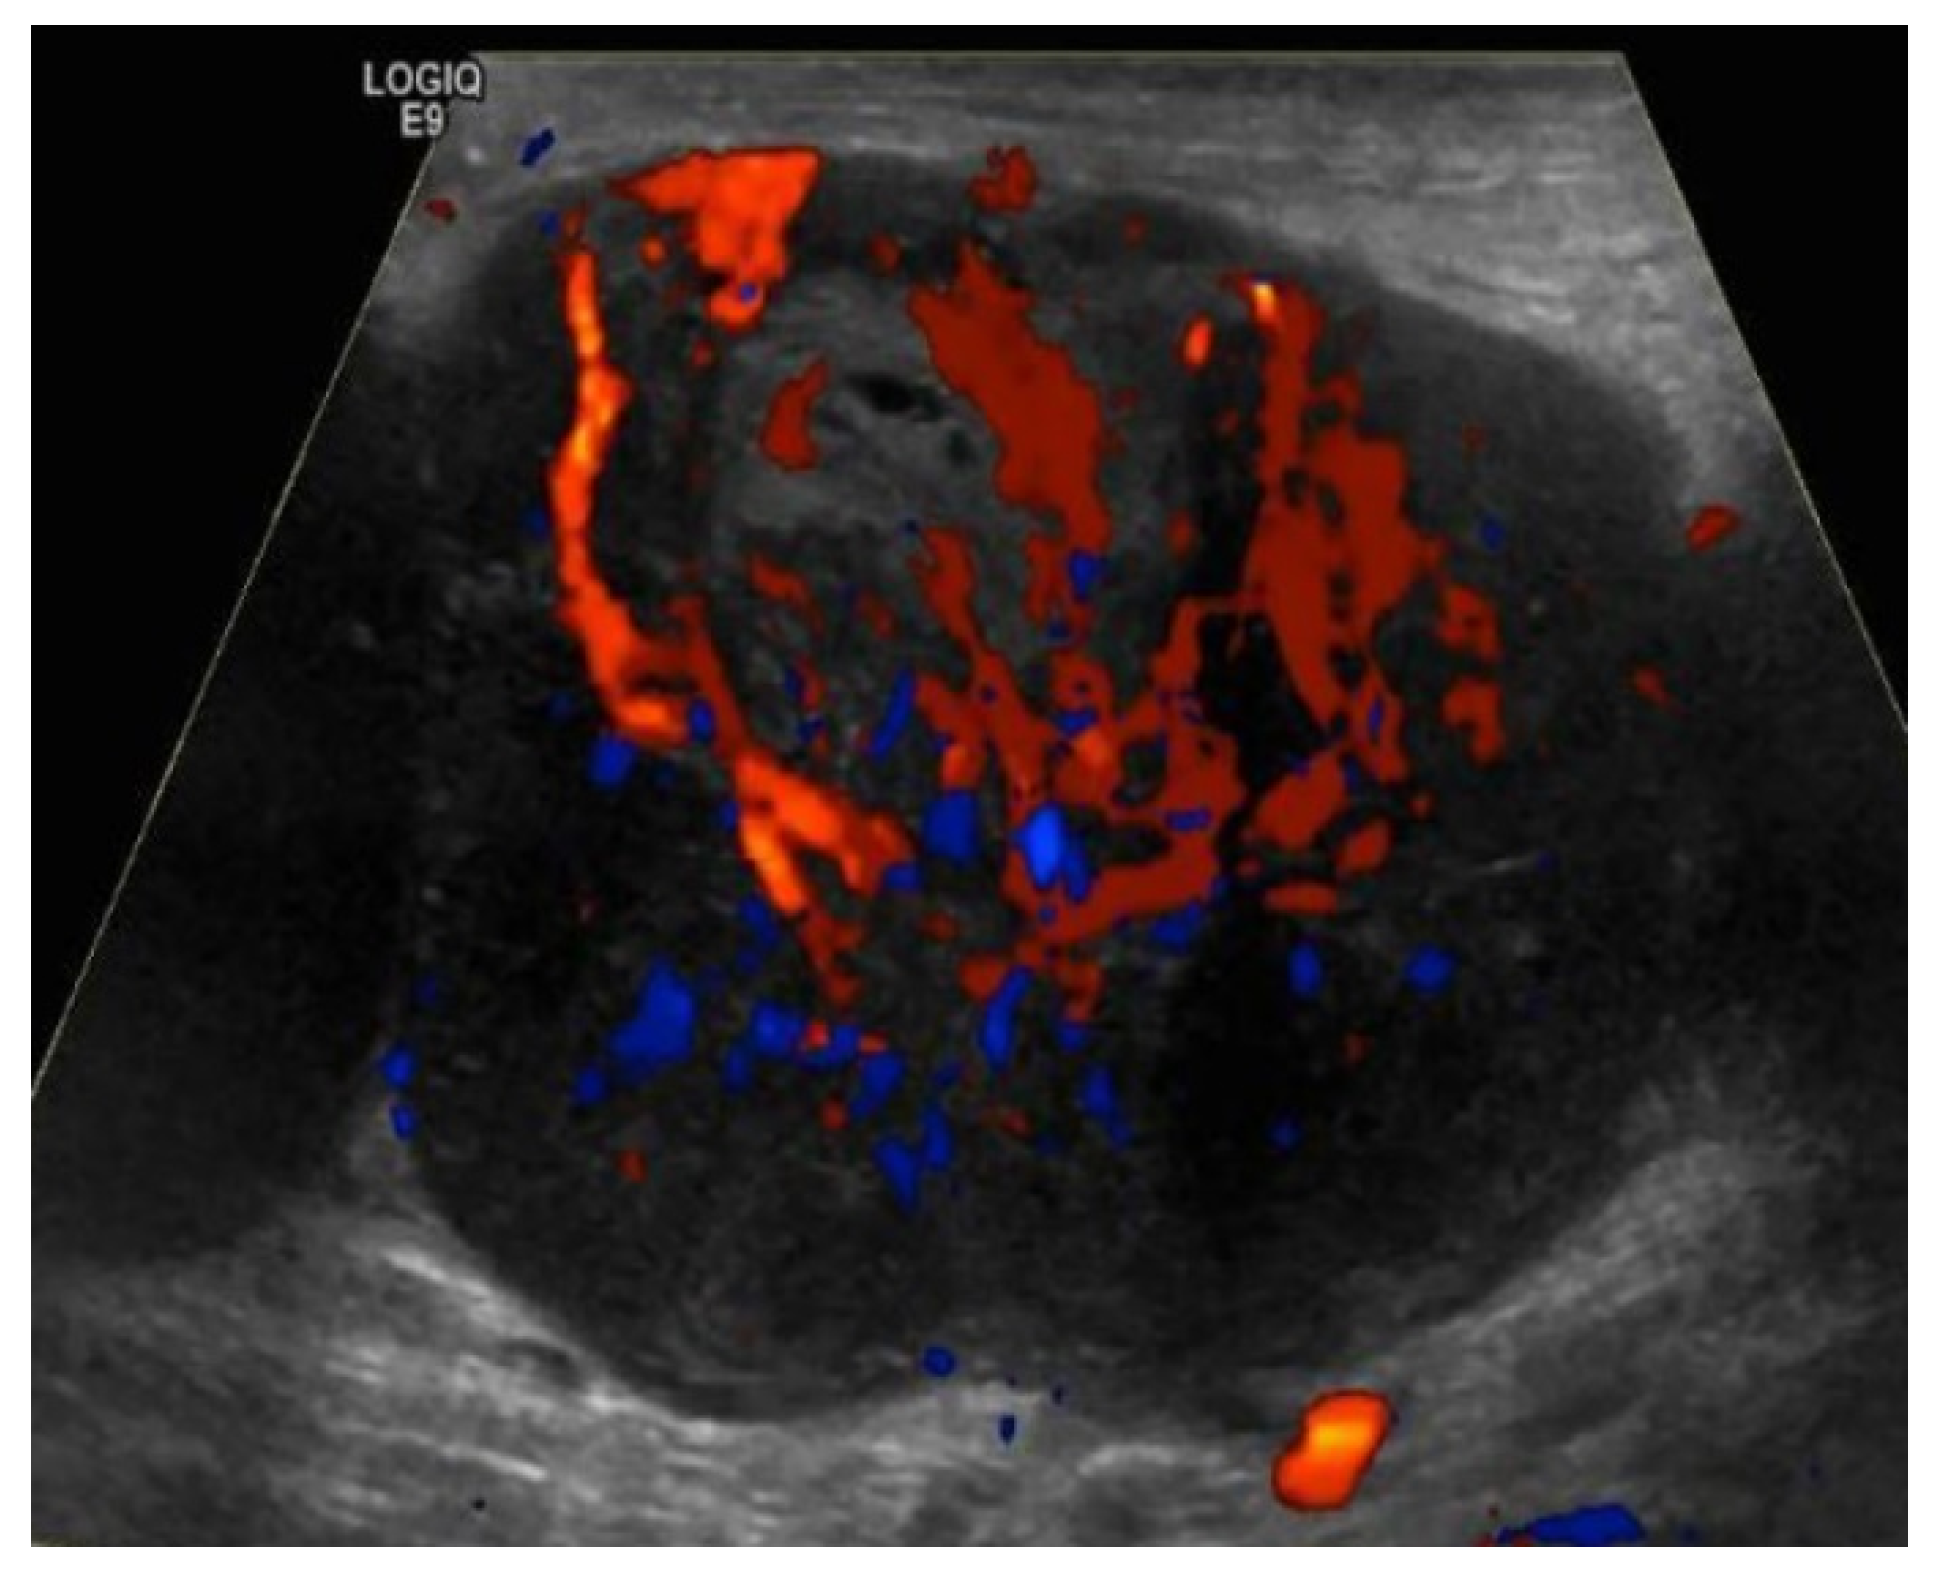

- Prativadi, R.; Dahiya, N.; Kamaya, A.; Bhatt, S. Chapter 5 Ultrasound Characteristics of Benign vs Malignant Cervical Lymph Nodes. Semin. Ultrasound CT MRI 2017, 38, 506–515. [Google Scholar] [CrossRef]

- Wang, B.; Zhang, M.K.; Zhou, M.P.; Liu, Y.; Li, N.; Liu, G.; Wang, Z.L. Logistic Regression Analysis of Conventional Ultrasound, and Contrast-Enhanced Ultrasound Characteristics. J. Ultrasound Med. 2021. [Google Scholar] [CrossRef]

- Dudea, S.M.; Lenghel, M.; Botar-Jid, C.; Vasilescu, D.; Duma, M. Ultrasonography of superficial lymph nodes: Benign vs. malignant. Med. Ultrason. 2012, 14, 294–306. [Google Scholar]

- Vassallo, P.; Wernecke, K.; Roos, N.; E Peters, P. Differentiation of benign from malignant superficial lymphadenopathy: The role of high-resolution US. Radiology 1992, 183, 215–220. [Google Scholar] [CrossRef]

- Ahuja, A.; Ying, M. Sonographic evaluation of cervical lymphadenopathy: Is power Doppler sonography routinely indicated? Ultrasound Med. Biol. 2003, 29, 353–359. [Google Scholar] [CrossRef]

- Ahuja, A.T. Ultrasound of malignant cervical lymph nodes. Cancer Imaging 2008, 8, 48–56. [Google Scholar] [CrossRef]

- Rubaltelli, L.; Khadivi, Y.; Tregnaghi, A.; Stramare, R.; Ferro, F.; Borsato, S.; Fiocco, U.; Adami, F.; Rossi, C.R. Evaluation of lymph node perfusion using continuous mode harmonic ultrasonography with a second-generation contrast agent. J. Ultrasound Med. 2004, 23, 829–836. [Google Scholar] [CrossRef]

- Cui, X.-W. New ultrasound techniques for lymph node evaluation. World J. Gastroenterol. 2013, 19, 4850–4860. [Google Scholar] [CrossRef] [PubMed]

| US Criteria | Benign Lymph Node | Malignant Lymph Node |

|---|---|---|

| Size | <1 cm in short axis | ≥1 cm in short axis |

| Shape | Oval or elliptical | Round |

| Border | Indistinct | Sharp |

| Echogenicity | Hypoechoic | Very hypoechoic |

| Hilum | Maintained fatty hilum | Absent fatty hilum |

| Vascularity | Avascular or hilar vascularity | Peripheral or mixed |

| Resistive index | Low | High |